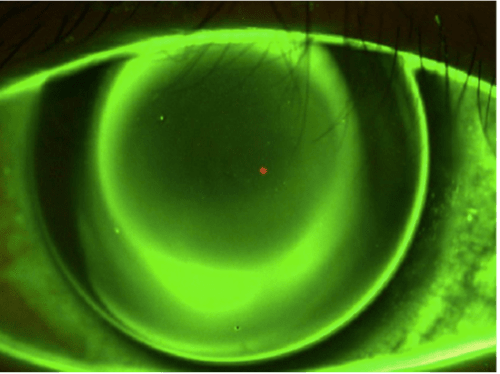

A first introduction into the way an orthokeratology lens should look like on an eye is often described as a “bullseye” pattern, with an area of touch centrally and a mid-peripheral reverse curve that lights up with sodium fluorescein (NaFl) under cobalt blue light. However, just because this is present doesn’t mean the fit is successful. A lens that is too shallow or a lens that has poor alignment in the mid-peripheral curves can still create a bullseye pattern.

When describing the central fit, the optical zone should be fairly centered over the pupil and some NaFl should crest over the cornea as the lens moves slightly on blink. If there is an area over which the NaFl is unable to glide, the lens may be too shallow, and the epithelium may be at risk for breakdown. On the contrary, if there is complete coverage with NaFl, the lens may be too deep, and proper epithelial molding may not take place. A consultant at a laboratory would be able to help make these adjustments to the lens design with descriptions of the central alignment and NaFl patterns.

Moving outward, look at both the reverse curve (illuminates with NaFl) and the alignment curve (absent of NaFl) rings. Both areas should have defined borders to the surrounding zones. NaFl from the reverse curve ring should not pump under the alignment curve; this usually indicates some toricity on the cornea that needs more (or less) toricity in the lens to better align to the cornea. Without proper sealing between these zones, the center molding effect may not take place, leaving the patient with subpar vision. Photos are helpful in describing this scenario. However, if a camera is not handy, communicating the meridian of poor alignment can be helpful when designing a new lens (Figures 1 and 2).